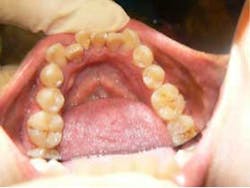

She came to me for an orthodontic consultation. She was 24 years old and hoping to marry her then-boyfriend at some point, but she didn't like her smile; she felt it was unattractive. So we gathered her orthodontic records and pointed out to her that it appeared she had either a supernumerary tooth or over-retained primary tooth between her upper centrals. Along with this, she also had some minor crowding on her lower teeth. She had a Class I molar relationship that I hoped to maintain.

Extraction of supernumerary tooth —